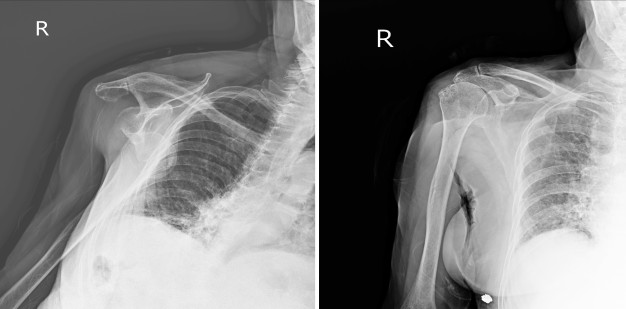

อาการปวดไหล่ (Shoulder pain) และ ข้อไหล่เคลื่อนหลุด (Shoulder sublaxation) เป็นอาการที่สอดคล้องและเกิดต่อเนื่องกัน พบได้มากในช่วงแรกของผู้ป่วยโรคหลอดเลือดสมองซึ่งเป็นช่วงที่กล้ามเนื้ออ่อนปวกเปียก (Flaccidity) ความตึงตัวของกล้ามเนื้อลดลง (Hypotone) ผู้ป่วยจะมีการเคลื่อนไหวของแขนลดลง เมื่อมีการเคลื่อนไหวของแขนไม่ถูกวิธีจะทำให้เอ็นกล้ามเนื้อ เยื่อหุ้มข้อไหล่ถูกดึงยืดทั้งจากแรงภายนอกและแรงโน้มถ่วงของโลก ทำให้ผู้ป่วยมีอาการปวดไหล่ได้ง่ายและอาจนำไปสู่การเกิดภาวะข้อไหล่เคลื่อนหลุด (Shoulder sublaxation) จากความตึงตัวของกล้ามเนื้อรอบข้อไหล่และความแข็งแรงของกล้ามเนื้อสะบักลดลง ทำให้ไม่สามารถพยุกกระดูกต้นแขน (Humerus bone) ให้อยู่ในเบ้าของกระดูกสะบัก (Glenoid fossa) ผู้ป่วยจึงอาจจะมีอาการ ปวดข้อไหล่ตลอดเวลาแม้ในขณะพัก

2.การใส่อุปกรณ์พยุงแขน หรือ Arm sling / Bobath sling

ควรใส่อุปกรณ์พยุงทุกครั้งเมื่อนั่งยืนเดินเพื่อไม่ให้แขนตกตามแรงโน้มถ่วงของโลก สามารถช่วยลดอาการปวดได้ ถ้าผู้ป่วยstrokeใส่ที่พยุงแขนตั้งแต่ช่วงแรกจะช่วงลดการเกิดsubluxation